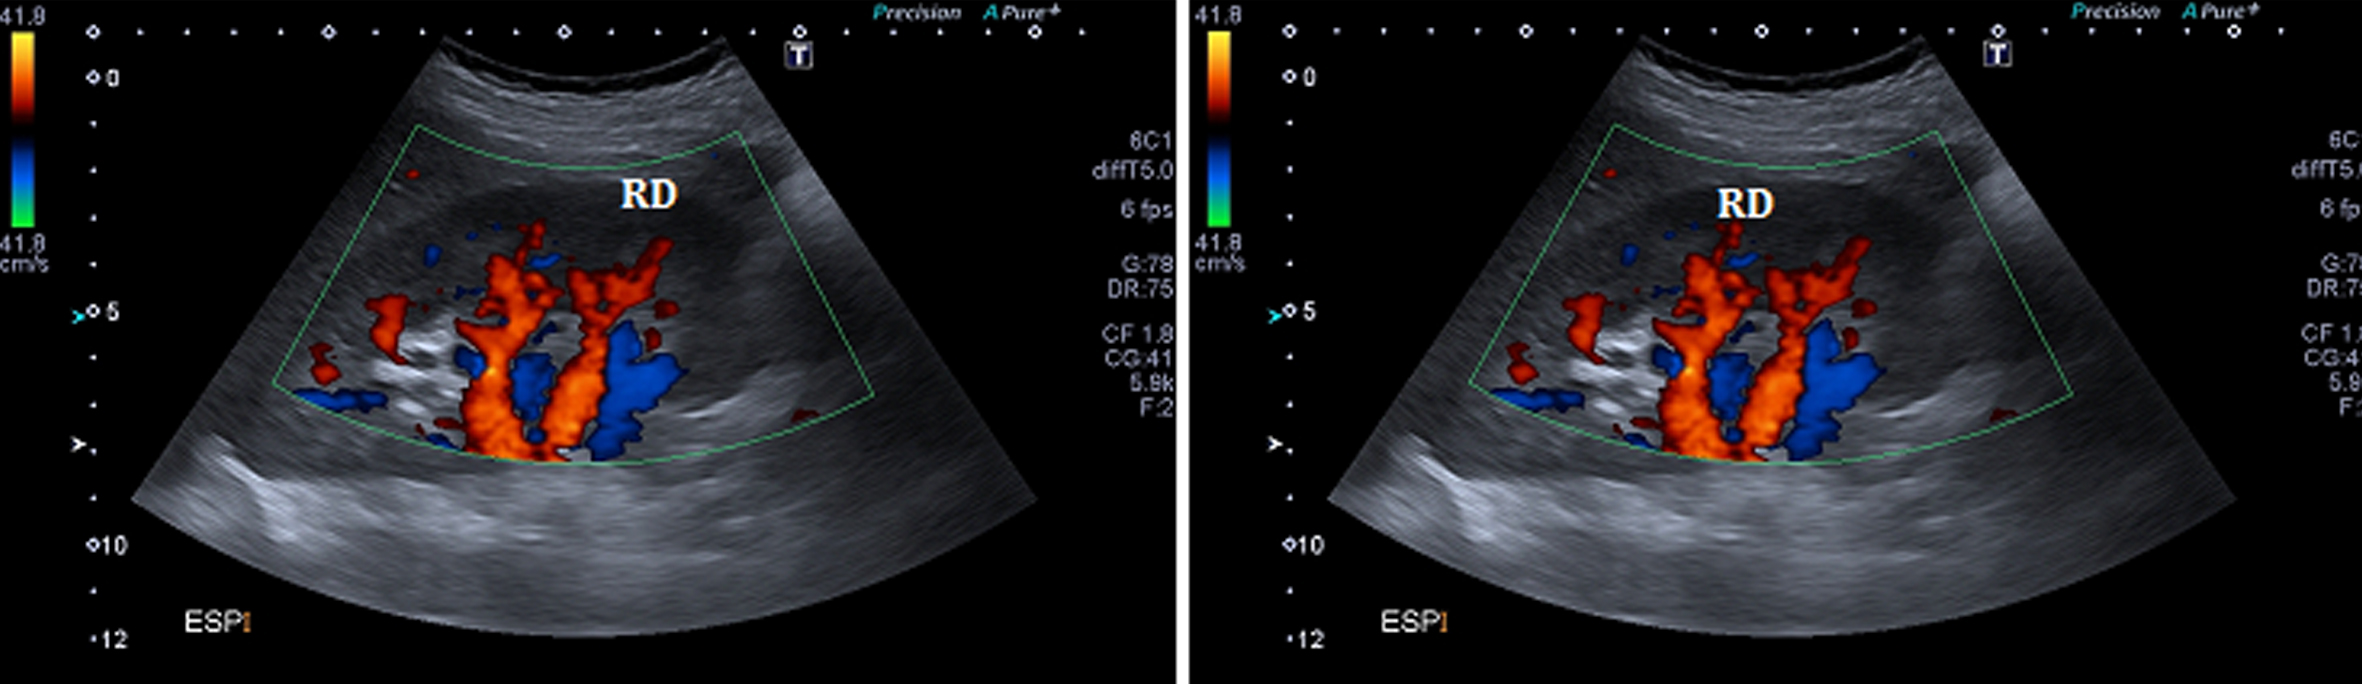

Figura 4

Ecografía Doppler, Cortes longitudinales. En espiración (izquierda) y en inspiración (derecha). (RD) Riñón derecho.

Se comprueba una aorta abdominal ectásica en toda su extensión, con velocidades sisto-diastólicas habituales (velocidad picosistólica de 70 cm/seg.). Ambos riñones son de forma y tamaño habitual, con parénquima de espesor y ecogenicidad normal y buena diferenciación córtico-medular bilateralmente. No se ven alteraciones de las cavidades excretoras. Se realiza estudio dinámico de las arterias renales durante el ciclo respiratorio el cual demuestra que durante la inspiración el sector proximal de la arteria renal derecha se “verticaliza”, quedando paralela a la aorta abdominal, (Fig. 5), comprobándose además aumento de las velocidades sisto-diastólicas en este sector de la arteria, con velocidades picosistólicas (VPS) de 385 cm/seg en inspiración, comportándose desde el punto de vista hemodinámico como una estenosis significativa.

En esta fase del ciclo se observa íntimo contacto entre el sector proximal de la arteria renal derecha y la crura diafragmática ipsilateral, en concordancia con lo visto por angioTC.

Durante la inspiración es también evidente una disminución significativa de la vascularización del riñón derecho, con ondas de flujo de tipo “tardus et parvus” a nivel intrarrenal compatible con flujo post-obstructivo (postestenótico). (Fig. 6)

En espiración la arteria tiene un trayecto horizontal y velocidades de flujo normales (VPS de 122 cm/seg) (Fig. 5), siendo la vascularización intrarrenal de distribución habitual y con patrones de flujo normales. (Fig. 4)